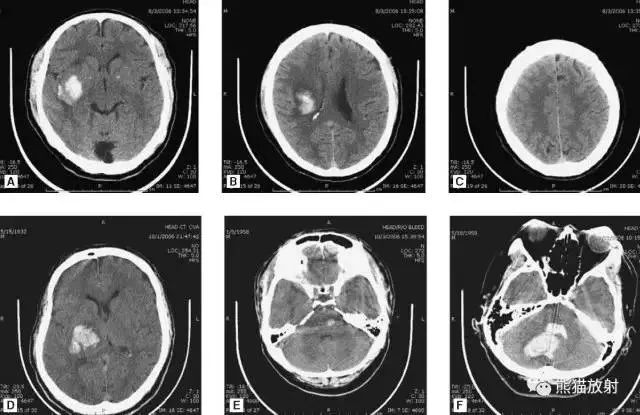

颅脑CT常用的三个窗(图A-C):图A:骨窗(the bone window)。

图B:脑窗(the brain window)。

图C:血窗(the blood window)。

图A:骨窗;主要用于明确骨折、窦腔病变、颅内积气。

图B:脑窗;可清晰显示灰白质,可发现中风的早期征象或其他导致脑水肿等表现的病变。

图C:血窗;更利于显示硬膜下或颅内出血。本例表现:骨窗示:右顶骨骨折;三个窗均示:软组织水肿并皮下积气;血窗:少量硬膜下血肿。